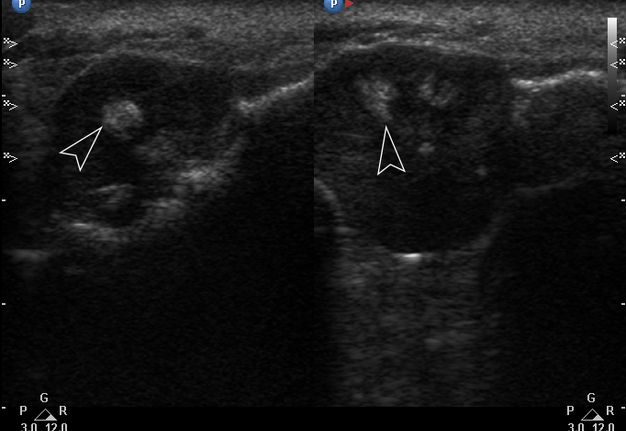

Gray-scale USG (Fig 4) revealed a unilocular, well-defined lesion with heterogeneous echogenicity. The lesion was measured 2.08 × 2.2 cm and located in a saddle-shaped position on the edentulous area of the anterior part of alveolar ridge of the mandible. The presence of multiple echoic areas and acoustic enhancement behind the neoplasm is noted.

FIGURE 4. Gray-scale ultrasound shows a unilocular, well-defined lesion with heterogeneous echogenicity. The lesion is measured 2.08 × 2.2 cm and indicated by “+” and “×” calipers. The lesion is located in a saddle-shaped position on the edentulous area of the anterior part of alveolar ridge of the mandible. Echoic area of bone formation is indicated by arrowhead. The area of the mandible on which the mass is located is indicated by an arrow and has a hyperechoic appearance. Acoustic enhancement is marked with an asterisk.

Color Doppler USG (Fig 5) showed prominent intralesional vascularity. Figure 6 demonstrates gray-scale USG of the lesion from two different angles, which allows for better visualization of echogenic areas (i.e., areas of ossification) within the lesion. It was not possible to adequately determine the area of the “stem” of the lesion.

FIGURE 6. Gray-scale sonograms of the lesion from two different angles (A, B). Sonograms show a hypoechoic lesion with multiple echoic areas (i.e., areas of bone formation). It is easy to distinguish areas of ossification (arrowheads) in the thickness of the lesion due to their echoic look. These two images demonstrate that gray-scale ultrasound is highly sensitive for detecting areas of ossification within a neoplasm such as PGCG.